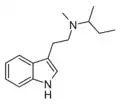

| NSBT | artificial | H | H | CH(CH3)CH2CH3 | N-sec-butyltryptamine | |

| MSBT | artificial | H | CH3 | CH(CH3)CH2CH3 | N-Methyl-N-sec-butyltryptamine | |